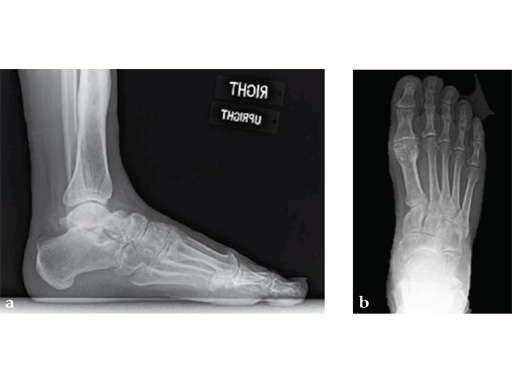

A 38-year-old man presented for opinion after two attempts to fuse the big toe MTP joint. The AP view is significant for luscency at the joint line. The lateral view is notable for loosening of the hardware and malposition because of the dorsiflexion built in to the precontoured implant. Revision was planned using a 0 variable angle locking/compression hallux MTP plate.

At 10 weeks postoperatively (see Fig. 2ab) the patient had no pain with weight bearing. The lateral view demonstrates improved position of the toe using a 0angle plate.